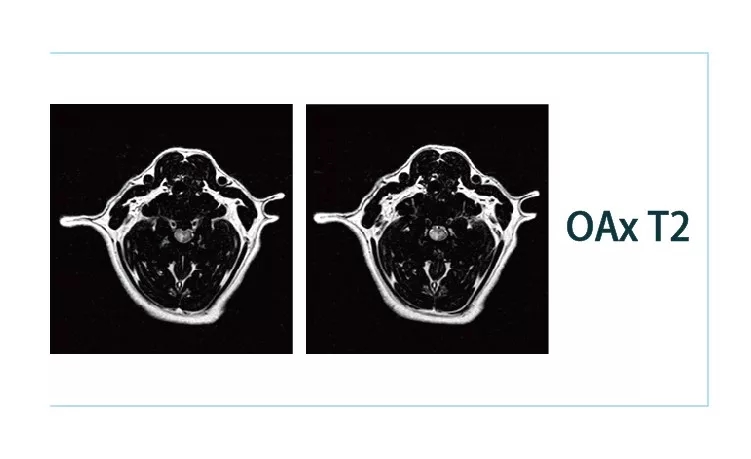

【朗润影像档案】20181221磁共振影像病例结果讨论